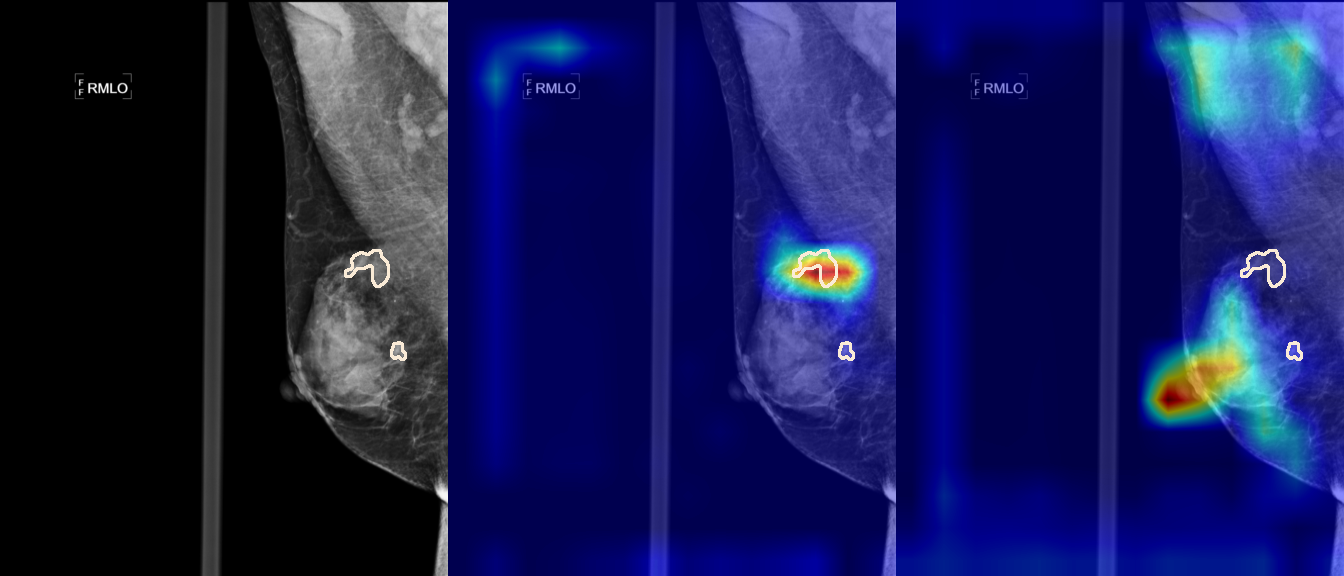

To interpret the decision-making process behind the quantitative results, we visualized Class Activation Maps (CAM) for the top-performing methods, ERM and VREx. Figures 1 through 2 illustrate discriminative regions identified by the models within the full mammograms.

Localization of Clinical Features: A key concern in medical AI is whether high performance stems from genuine pathology detection or spurious background correlations. Our visualizations suggest that Standard ERM achieves its superior quantitative performance by predominantly prioritizing clinical cues. As shown in the top rows of the Figure 1 and Figure 2, the ERM-trained models consistently focus attention on the specific lesion regions within the breast tissue. This demonstrates that despite lacking explicit invariance constraints, ERM is capable of learning robust, medically relevant features when trained on diverse multi-source data.

Attention Drift in Both Methods: While both ERM and VREx generally identify the correct region of interest in successful cases, neither method is immune to attention drift. We observe instances in both training paradigms where the model focuses on irrelevant areas, such as healthy fibroglandular tissue or background artifacts (e.g., rows 5 and 6 in Figure 1). This indicates that while VREx is designed to penalize instability, it does not guarantee perfect anatomical focus compared to the unconstrained ERM baseline.